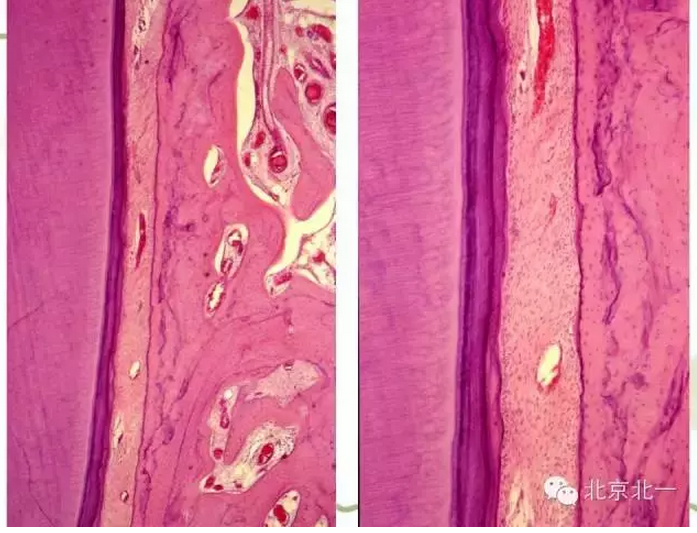

【牙周學(xué)習(xí)】牙周組織--基礎(chǔ)知識(shí)篇(下)